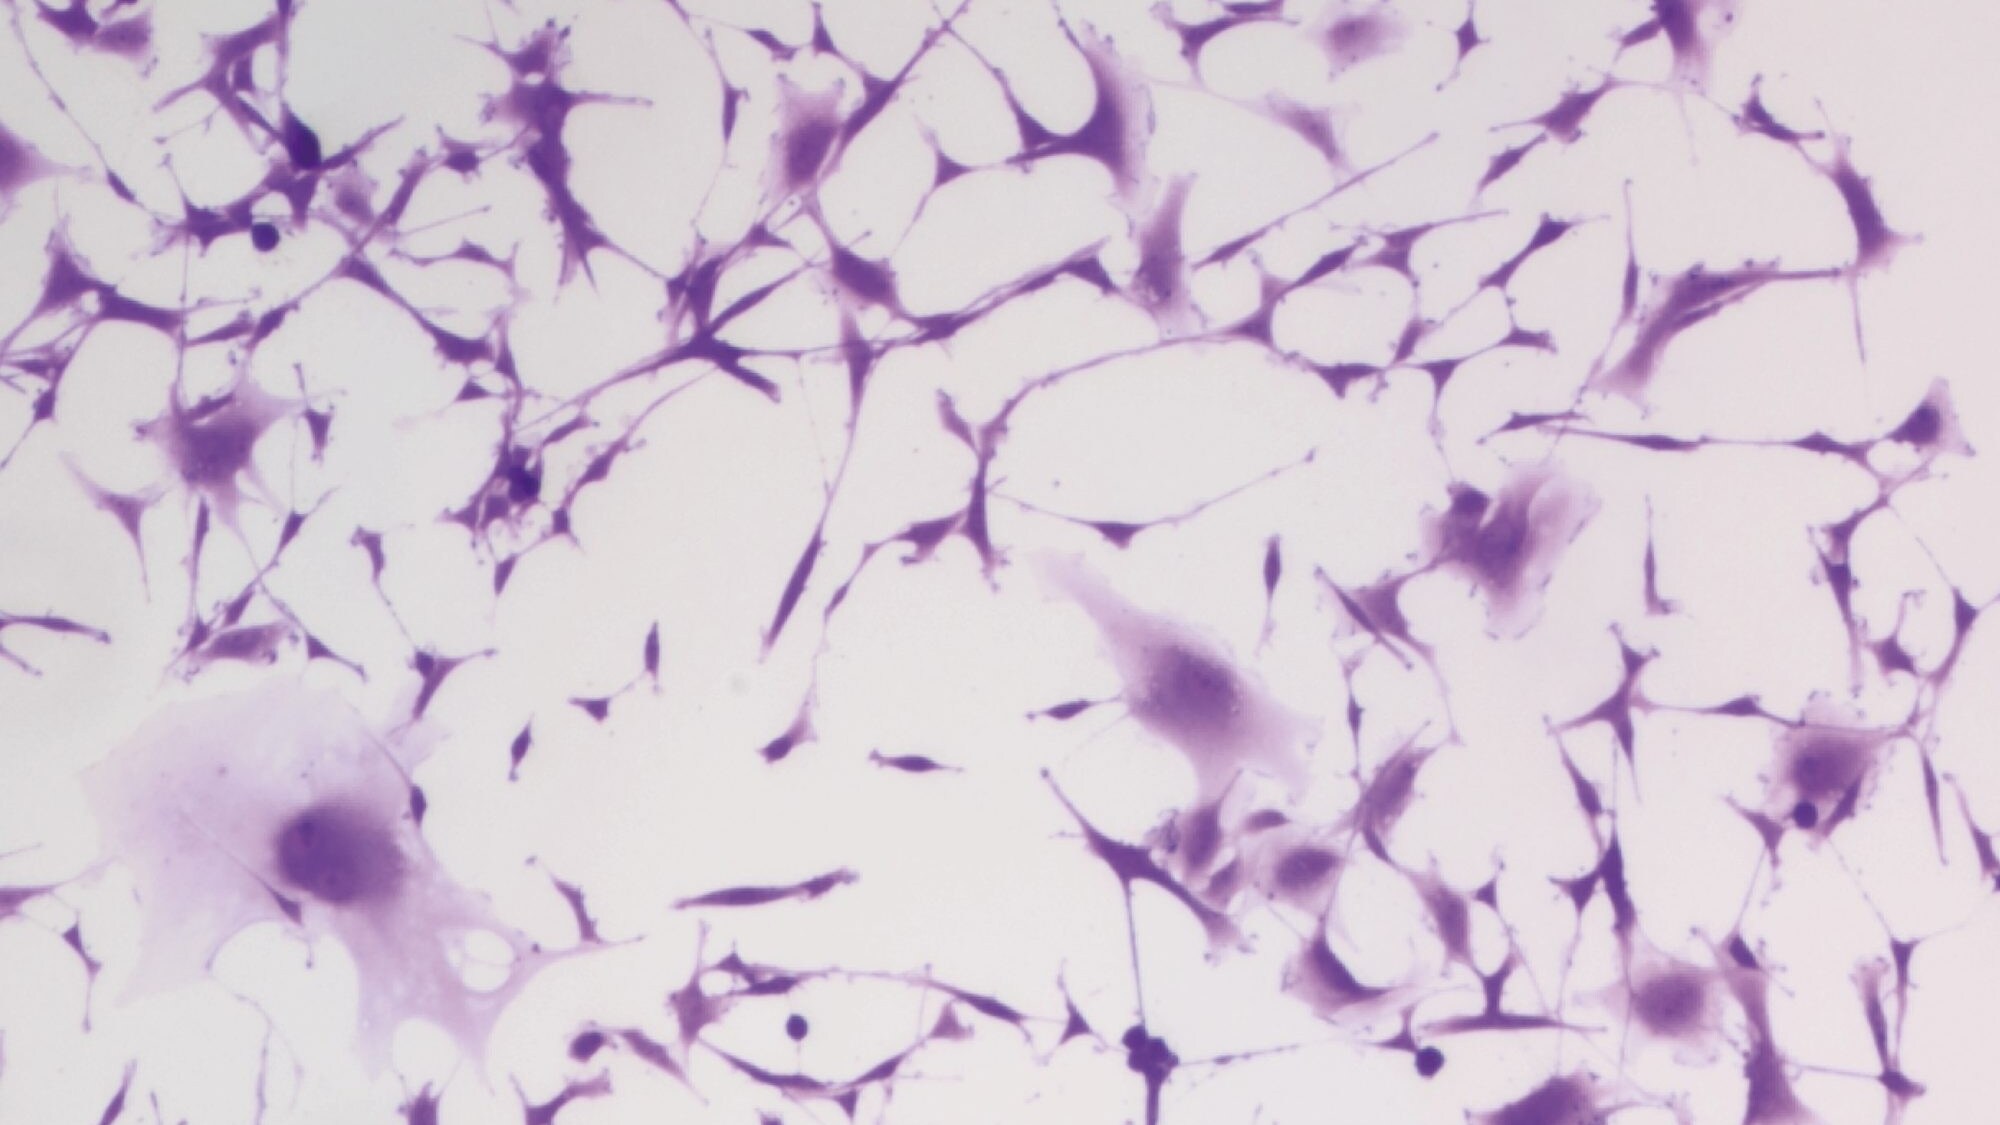

Nel corso degli esperimenti il 50% delle cellule maligne sono state eliminate, peraltro utilizzando una piccola quantità di cannabinoidi, la quale non può portare ad effetti collaterali. L'effetto di queste ultime sostanze è quello di rendere i tumori più sensibili alle radiazioni del trattamento anti-tumorale, una scoperta importantissima perché le cellule maligne presenti nel cervello sono quasi impossibili da eliminare.

"Pensiamo che i principi attivi della marijuana siano in grado di segnalare le cellule maligne e ‘prepararle' al successivo trattamento classico" ha continuato Liu "L'assunzione preventiva di cannabis sembra interferire con l'abilità delle cellule tumorali di riparare il danno creato dalle radiazioni".